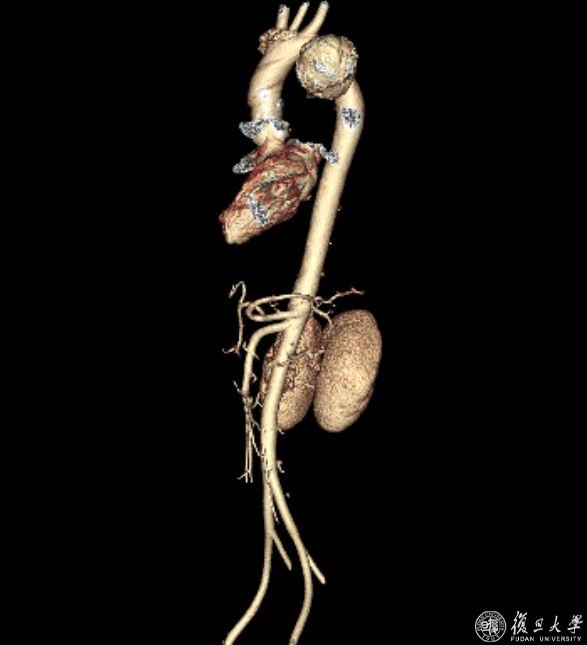

抵达上海的当日中午,格桑旦增病症骤然加重,由痰中带血迅速发展为咯血,心急如焚的姐姐联系了血管外科董智慧教授和方刚医生。董教授和方医生初步判断可能为胸主动脉假性动脉瘤破裂,一旦破裂发生,很可能会导致主动脉大出血及主动脉-支气管瘘,进一步诱发失血性休克,从而导致死亡,因此建议患者立刻至血管外科急诊就诊。血管外科总值班方圆医生立即为格桑旦增进行主动脉CTA检查,发现一颗巨大的假性动脉瘤盘踞在胸主动脉,万幸的是,瘤体尚显完整,暂无破裂征象,然而,这颗巨大的假性动脉瘤就像一颗不定时血管“炸弹”,在其爆炸之前拆除它是当前的第一要务。情况紧急,为便于生命体征监测及可能发生的急重症抢救,急诊立即将格桑旦增收治入监护室,暂时稳住了病情。

巨大的胸主动脉假性动脉瘤

4月28日下午,血管外科符伟国教授、董智慧教授、石赟教授、方刚医生、王峰医生、邹凌威博士共同为格桑旦增实施了胸主动脉腔内修复术,同时,为尽量保留较优势的左侧椎动脉,采用了原位开窗技术重建左锁骨下动脉,使用了符伟国教授原创设计的Fustar可调弯鞘等专用器材。该核心器械为主动脉弓部腔内病变的患者带来了更安全、有效的腔内介入解决方案,已获国际发明专利,并通过美国FDA和欧盟CE认证,销往欧美14个国家和地区。

最终,手术顺利完成,即刻造影显示动脉瘤已消失,胸主动脉弓上分支血管血流畅通。术后,格桑旦增咯血症状消失,术后一天即可下床活动,恢复良好,目前已顺利出院。出院两周之后的复查中显示支架保持通畅,动脉瘤隔绝良好,瘤腔内已完全血栓化。格桑旦增也终于松了一口气,可以放心地长途飞行返回西藏了。